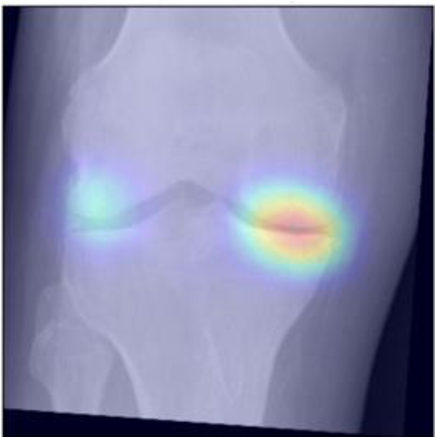

To gain insight into the basis of the CNN’s prediction, we used the GradCAM [24] approach and visualized the attention maps for the well-predicted knees. Examples of attention maps are presented in Figure 5. We observed that in various cases, the CNN paid attention to the compartment opposite to the one where degenerative change became visible during the follow-up visits. Additional examples of such attention maps are presented in Supplementary Figures 3, 4, 5 and 6.

Refer to caption

(a)

(b)

(c)

(d)

Figure 5: Examples of attention maps for progression cases and the corresponding visualization of progression derived using follow-up images from MOST datasets. Here, subplots (a) and (c) show the attention maps derived using a GradCAM approach. Subplots (b) and (d) show the joint-space areas from all the follow-up images (baseline to 84 months). Here, the subplot (b) corresponds to the attention map a) and the subplot (d) corresponds to the attention map (c).